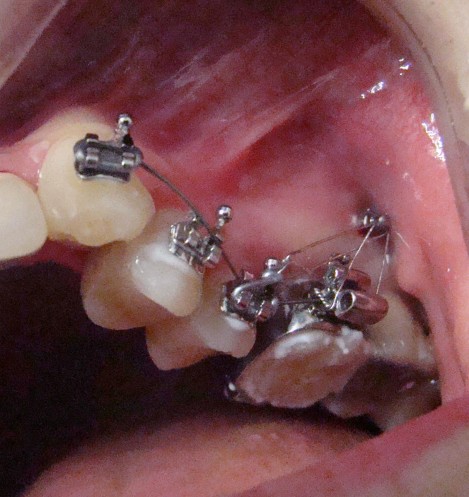

Предимства на методите на лечение с интраоралния фиксиран апарат M-Pendulum

За да се достигне до решение за избор на екстракционно или безекстракционно оротодонтско лечение е необходимо да се съобразим с недостига на място в зъбната дъга и продължителността на лечението. За това си поставихме за цел да съпоставим тези параметри.

Клинични аспекти при прилагане на апарата Pendulum в смесено съзъбие

В тази статия си поставяме за цел да разискваме от клинична гледна точка позитивите и негативите при ползване на апарата Pendulum в смесено съзъбие. Ще разгледаме становищата за работа с апарата в случаите, когато са включени временните молари като опорна зона. Ще дадем какви са според нас клиничните предпоставки и индикации за използването на Pendulum в смесено съзъбие.